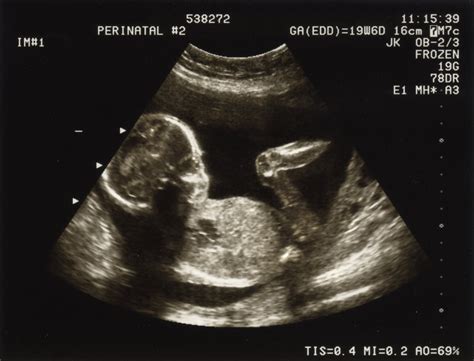

Săptămânile 16-18

Fătul măsoară 16 cm și cântărește 200 grame. Încep să fie simțite primele mișcări active fetale. Este un moment oportun pentru o ecografie, la care poate participa și partenerul.

Săptămânile 19-21

La jumătatea sarcinii, urechea fătului poate distinge zgomote și tonalități. Fătul își dezvoltă preferințe muzicale și reacționează la stimuli auditivi. Cresc sprâncenele și genele, pielea este translucidă și increțită. Fătul cântărește aproximativ 400 grame. Burtica este vizibilă și purtată cu mândrie.